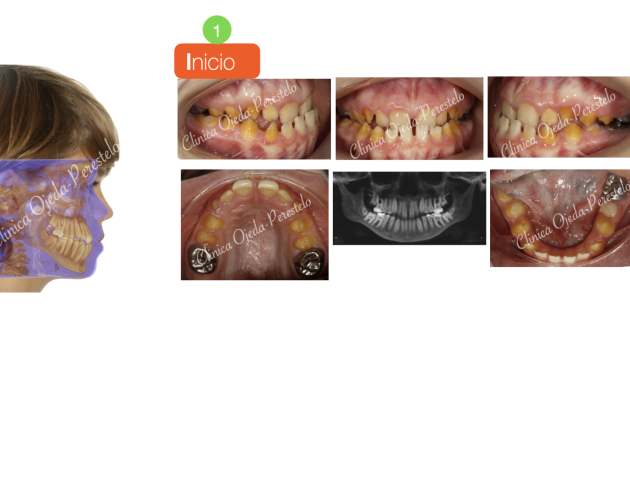

Clase III esquelética en dentición temporal Casos de Éxito - Niños